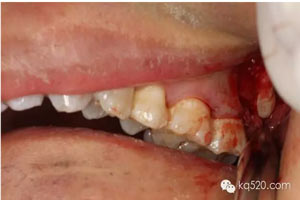

圖1.術(shù)前口內(nèi)像:上頜結(jié)節(jié)后份有一溢膿的瘺道,看不到28。

圖8.去骨后,可見(jiàn)28的牙冠,牙冠合面朝向遠(yuǎn)中水平。